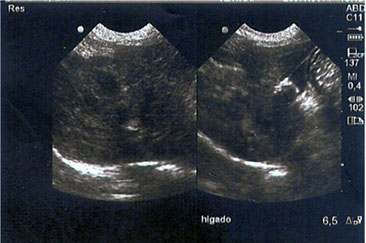

Se realizaron radiografías laterolateral y ventrodorsal de abdomen donde se apreció una silueta hepática disminuida en tamaño y los demás órganos aparentemente normales (Figura 3). Adicionalmente, se realizó una ecografía abdominal simple confirmándose el tamaño disminuido del hígado (Figura 4), parénquima y ecogenicidad dentro de parámetros normales y demás órganos abdominales aparentemente normales.

Figura 4. Ecografía abdominal donde se apreció que el hígado se observaba con parénquima normal y ecogenicidad dentro de parámetros normales, pero disminuido su tamaño.